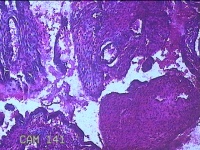

宫腔内容物

性别

女

年龄

42岁

临床诊断

异常子宫出血;贫血

一般病史

阴道流血半个月。

标本名称

大体所见

灰白暗红色不规则碎组织2.3x2x0.8cm一堆。

图2